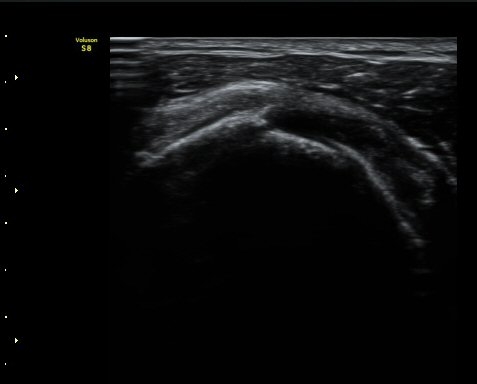

¾î±ú ¾Õ À̵ιڱ٠Ⱦ´Ü¸é°Ë»ç¿¡¼­ ÀÌºÎ¹Ú±Ù°Ç °í¶û ¾Æ·¡ ºÎÀ§¿¡¼­ À̵ιڱ٠ÀåµÎ ÁÖÀ§¿¡

¼ö¾×Àú·ù°¡ °üÂûµÈ´Ù(±×¸² 1, 2). °ß°©ÇÏ±Ù°Ç Á¾´Ü¸é°Ë»ç¿¡¼­ °ß°©ÇϱٰÇÀÇ °üÀý³»ºÎÀ§(±×¸² 3)